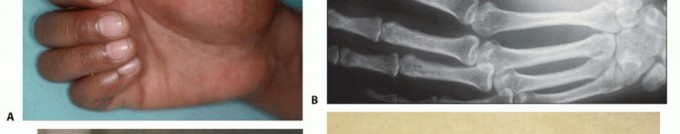

FIG 2 • A. Clinical picture and (B) plain radiograph showing metastatic carcinoma of lung to the mid-ulna with extensive bone destruction and soft tissue extension. C,D. Plain radiographs showing high-grade sarcoma of the proximal radius associated with extensive soft tissue extension. These tumors necessitate above-elbow amputation to achieve local tumor control and palliate pain.